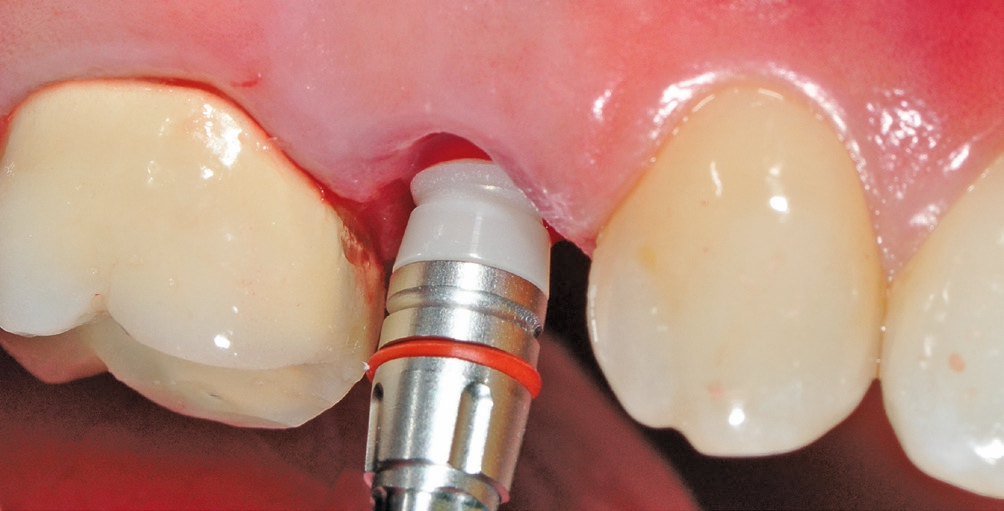

Nach sorgfältiger Kürettage und Inspektion einer idealen Knochenalveole vom Typ I [11] konnte mit der Sofortimplantation begonnen werden. Die ersten beiden Pilotbohrungen wurden teilnavigiert mit der Bohrschablone durchgeführt. Das restliche Bohrprotokoll wurde nach den Vorgaben des Herstellers frei durchgeführt. Mit der Insertion des Implantats konnte die nötige Primärstabilität von 35 Ncm für eine sofortige provisorische Versorgung erreicht werden. Im Vorfeld war ein Situationsmodell der Ausgangssituation und darauf eine Tiefziehschiene vorbereitet worden, die jetzt für die intraorale Herstellung des Provisoriums mit fließfähigem Kompositmaterial verwendet wurde. Als stabilisierende Gerüststruktur diente dabei die präzise sitzende Einbringkappe (insertion.transfer) auf dem Implantatkopf, die zuvor auf die entsprechende Höhe eingekürzt worden war. Nach der Ausarbeitung und okklusalen Adjustierung der Krone wurde diese provisorisch zementiert.